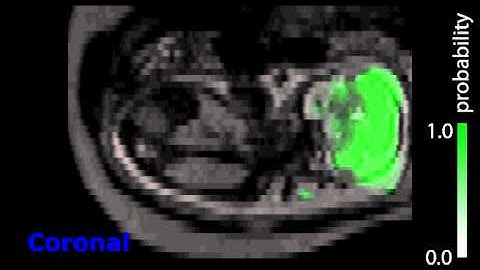

Kevin Keraudren: Localising organs of the fetus in MRI data using Python